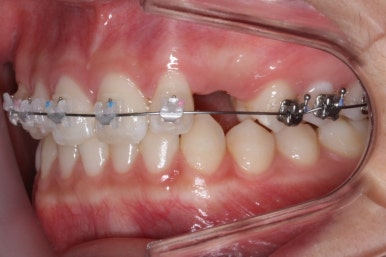

이번 환자분의 경우는 아랫니는 약간 삐뚤함이 있지만 굳이 교정치료를 원하지 않으셨기 때문에 윗니들만 부분교정으로 해결하기로 했습니다.

이상적으로라면 위-아래를 한 쌍으로 해야 교합을 맞추기에 유리하지만 이번의 경우는 윗니만 해도 충분히 교합을 맞출 수 있겠다고 판단하여 부분교정을 하였습니다.

윗니만 하고 싶다고 무조건 윗니 부분교정이 가능한 것이 아니기 때문에 반드시 교정전문의와의 상의를 추천드립니다.

부산매복치아교정 한 지 15개월만에 거의 제위치를 찾아가고 있는 모습입니다.

이번에도 매우 섬세한 조절을 위해 송곳니에는 철사가 두 줄로 연결되어 있기도 합니다.

어금니에는 일시적으로 치아를 띄워주기 위해 바이트레진이라는 것을 올리게 됩니다.

치아를 띄워주지 않으면 안쪽에 있던 송곳니를 바깥으로 데리고 나올 때 걸려서 못나오는 상황이 생길 수도 있기 때문입니다.